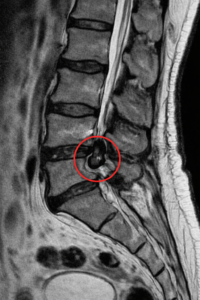

MRIの検査で椎間板が脊柱管内に落ち込む

いわゆる遊離(ゆうり)の状態で狭窄していました。